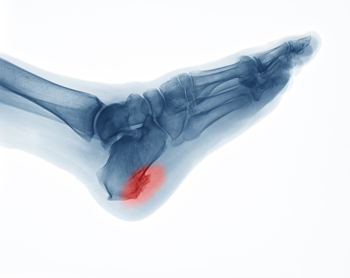

Recovery Tips for a Stress Fracture

stress fracture is defined as a hairline fracture that is generally the result of stress the bones endure from high impact activities such as running.  Because of this, the feet and lower legs are often susceptible to developing a stress fracture.  It is beneficial to implement adequate recovery procedures, despite the fact that many athletes choose to run through the pain and discomfort. A full recovery often begins with refraining from running for approximately four to six weeks, in addition to performing strengthening and flexibility exercises. If the stress fracture is severe, a boot may be worn for stability as the healing process occurs. If you have pain in your foot that increases gradually, it is strongly suggested that you visit a podiatrist who can diagnose and treat any potential stress fractures.

Dealing with Stress Fractures of the Foot and Ankle

Stress fractures occur in the foot and ankle when muscles in these areas weaken from too much or too little use.  The feet and ankles then lose support when walking or running from the impact of the ground. Since there is no protection, the bones receive the full impact of each step. Stress on the feet can cause cracks to form in the bones, thus creating stress fractures.

Pain from the fractures occur in the area of the fractures and can be constant or intermittent. It will often cause sharp or dull pain with swelling and tenderness. Engaging in any kind of activity which involves high impact will aggravate pain.